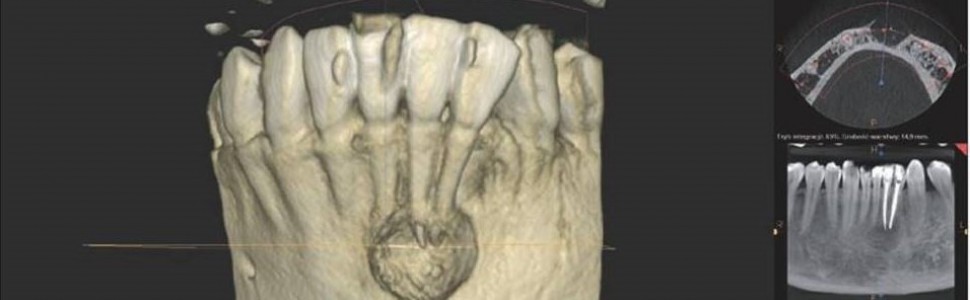

Pacjent zgłosił się ponownie dopiero po roku!, w marcu 2015 roku (pracował za granicą). Dolegliwości ustąpiły, aczkolwiek odczuwał pewne „drętwienie” tej okolicy. Zęby ponownie otwarto, wypełniono kanały metodą kondensacji bocznej gutaperki, zamknięto płynnym kompozytem oraz szkło‑jonomerem i wykonano badanie tomografii komputerowej wiązki stożkowej tej okolicy (ryc. 2, 3, 4), które ujawniło duży ubytek kostny okolicy wierzchołków korzeni zębów 32, 31, 41 z utratą blaszki wargowej części zębodołowej żuchwy, odpowiadający obrazowi torbieli korzeniowej.

Pacjent zgłosił się po tygodniu w celu usunięcia szwów. Rana goiła się prawidłowo. W opisie badania histologicznego wysłanego materiału potwierdzono wstępną diagnozę cystis odontogenes. Kontrolne badanie tomograficzne wykonano po  6 miesiącach, wykazało ono pełną odbudowę kostną ubytku (ryc. 6, 7, 8, 9). Pacjent od czasu zabiegu nie odczuwał żadnych dolegliwości w tej okolicy.